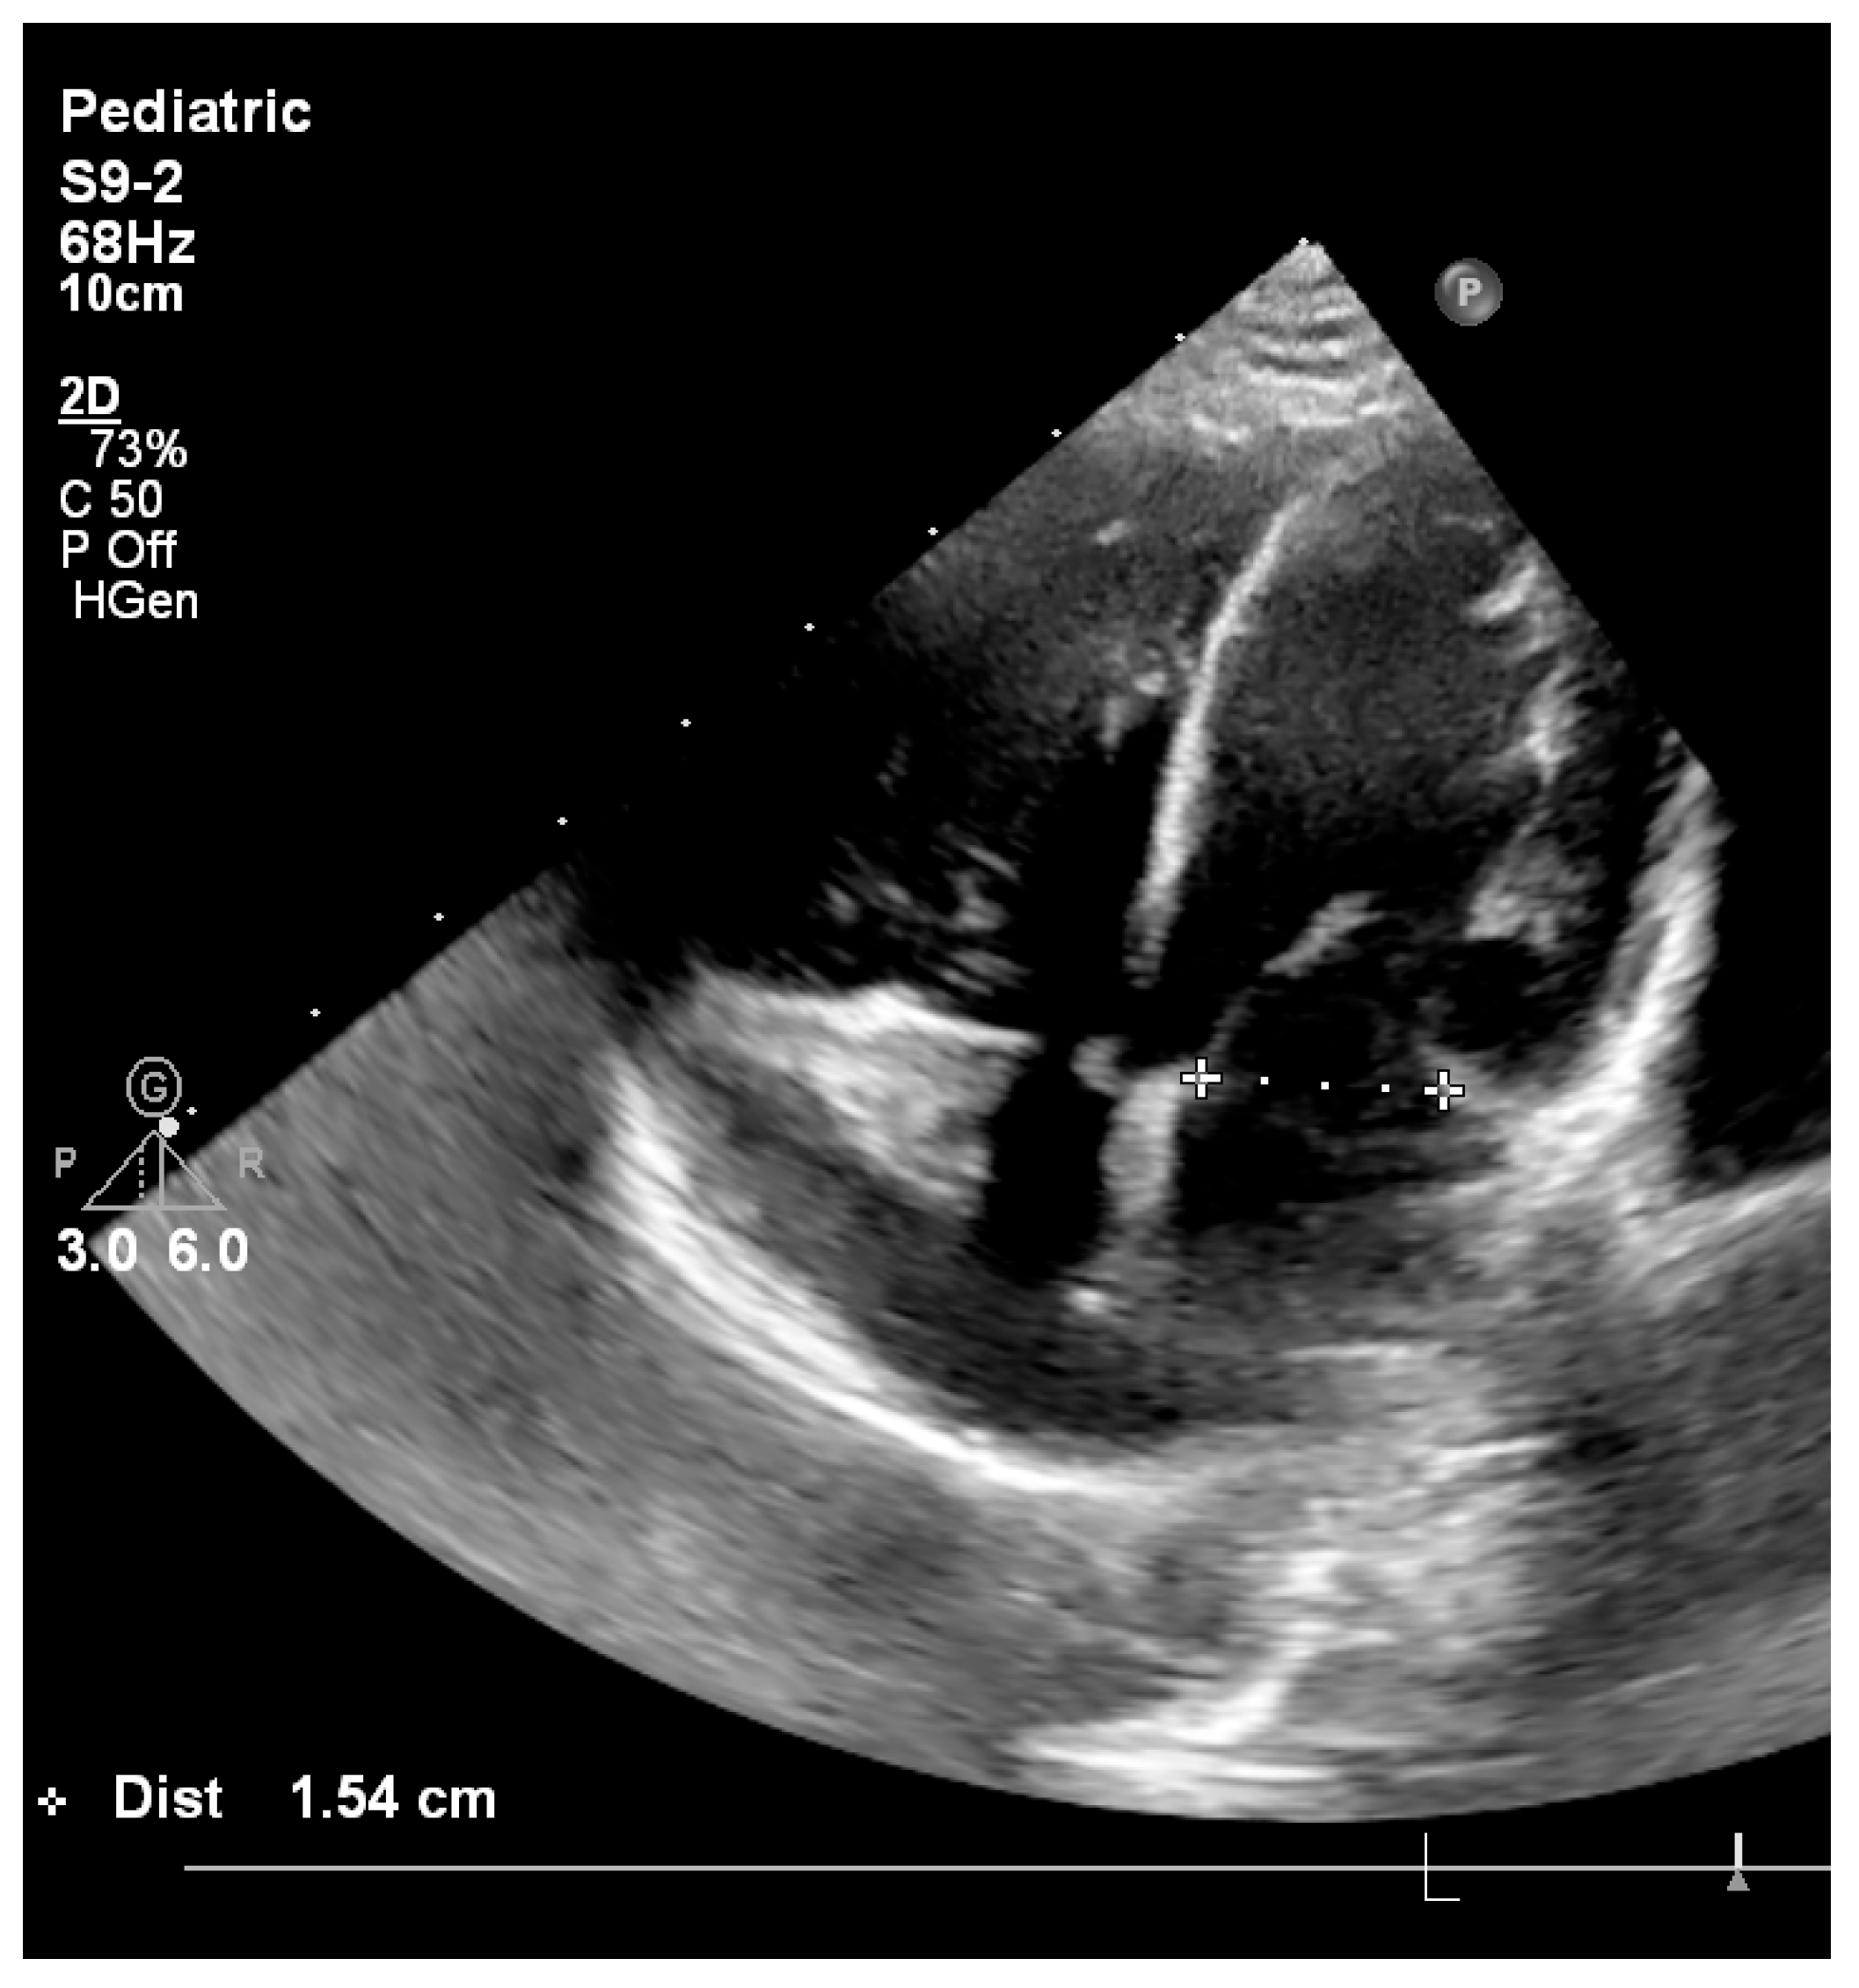

| Mitral valve Z-score | −4.57 | −4.40 | −4.64 | Normal: −2 to +2; Z-score < −3 associated with unfavorable anatomy for primary biventricular repair |

| Aortic annulus Z-score | −3.36 | −3.30 | −3.28 | Normal: −2 to +2; Z-score < −3 indicates severe hypoplasia |

| Mitral valve annulus (mm) | 8.5 | 8.7 | 15.4 |

| Mitral valve z-score | −4.1 | −4.0 | −0.6 |

| Aortic valve annulus (mm) | 5.9 | 6 | 10 |

| Aortic valve z-score | −3.5 | −3.5 | +1.3 |